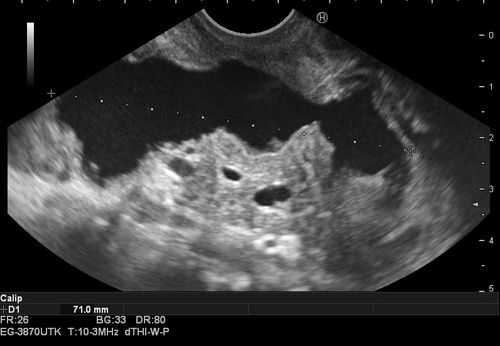

1. Проведение в желудок эхоэндоскопа OlympusGF-UE 160 и эндоскопическое ультразвуковое сканирование органов брюшной полости для определения зоны контакта стенки кисты со стенкой желудка (рис. 1). Рис. 1. Эхоэндоскопия и ультразвуковая визуализация панкреатической псевдокисты в теле поджелудочной железы (случай 1).

ПК локализовались в теле ПЖ у 7 (30,4%) пациентов, в хвосте ПЖ — у 7 (30,4%), в головке ПЖ — у 6 (26,2%) (рис. 1). Рис. 1. Псевдокиста головки поджелудочной железы (изображение при ультразвуковом исследовании). Стрелками указаны полость псевдокисты (1), бессосудистая зона (2). The arrows indicate pseudocyst cavity (1), avascular zone (2). У 3 (1%) больных имело место сочетанное расположение ПК в головке и теле ПЖ.